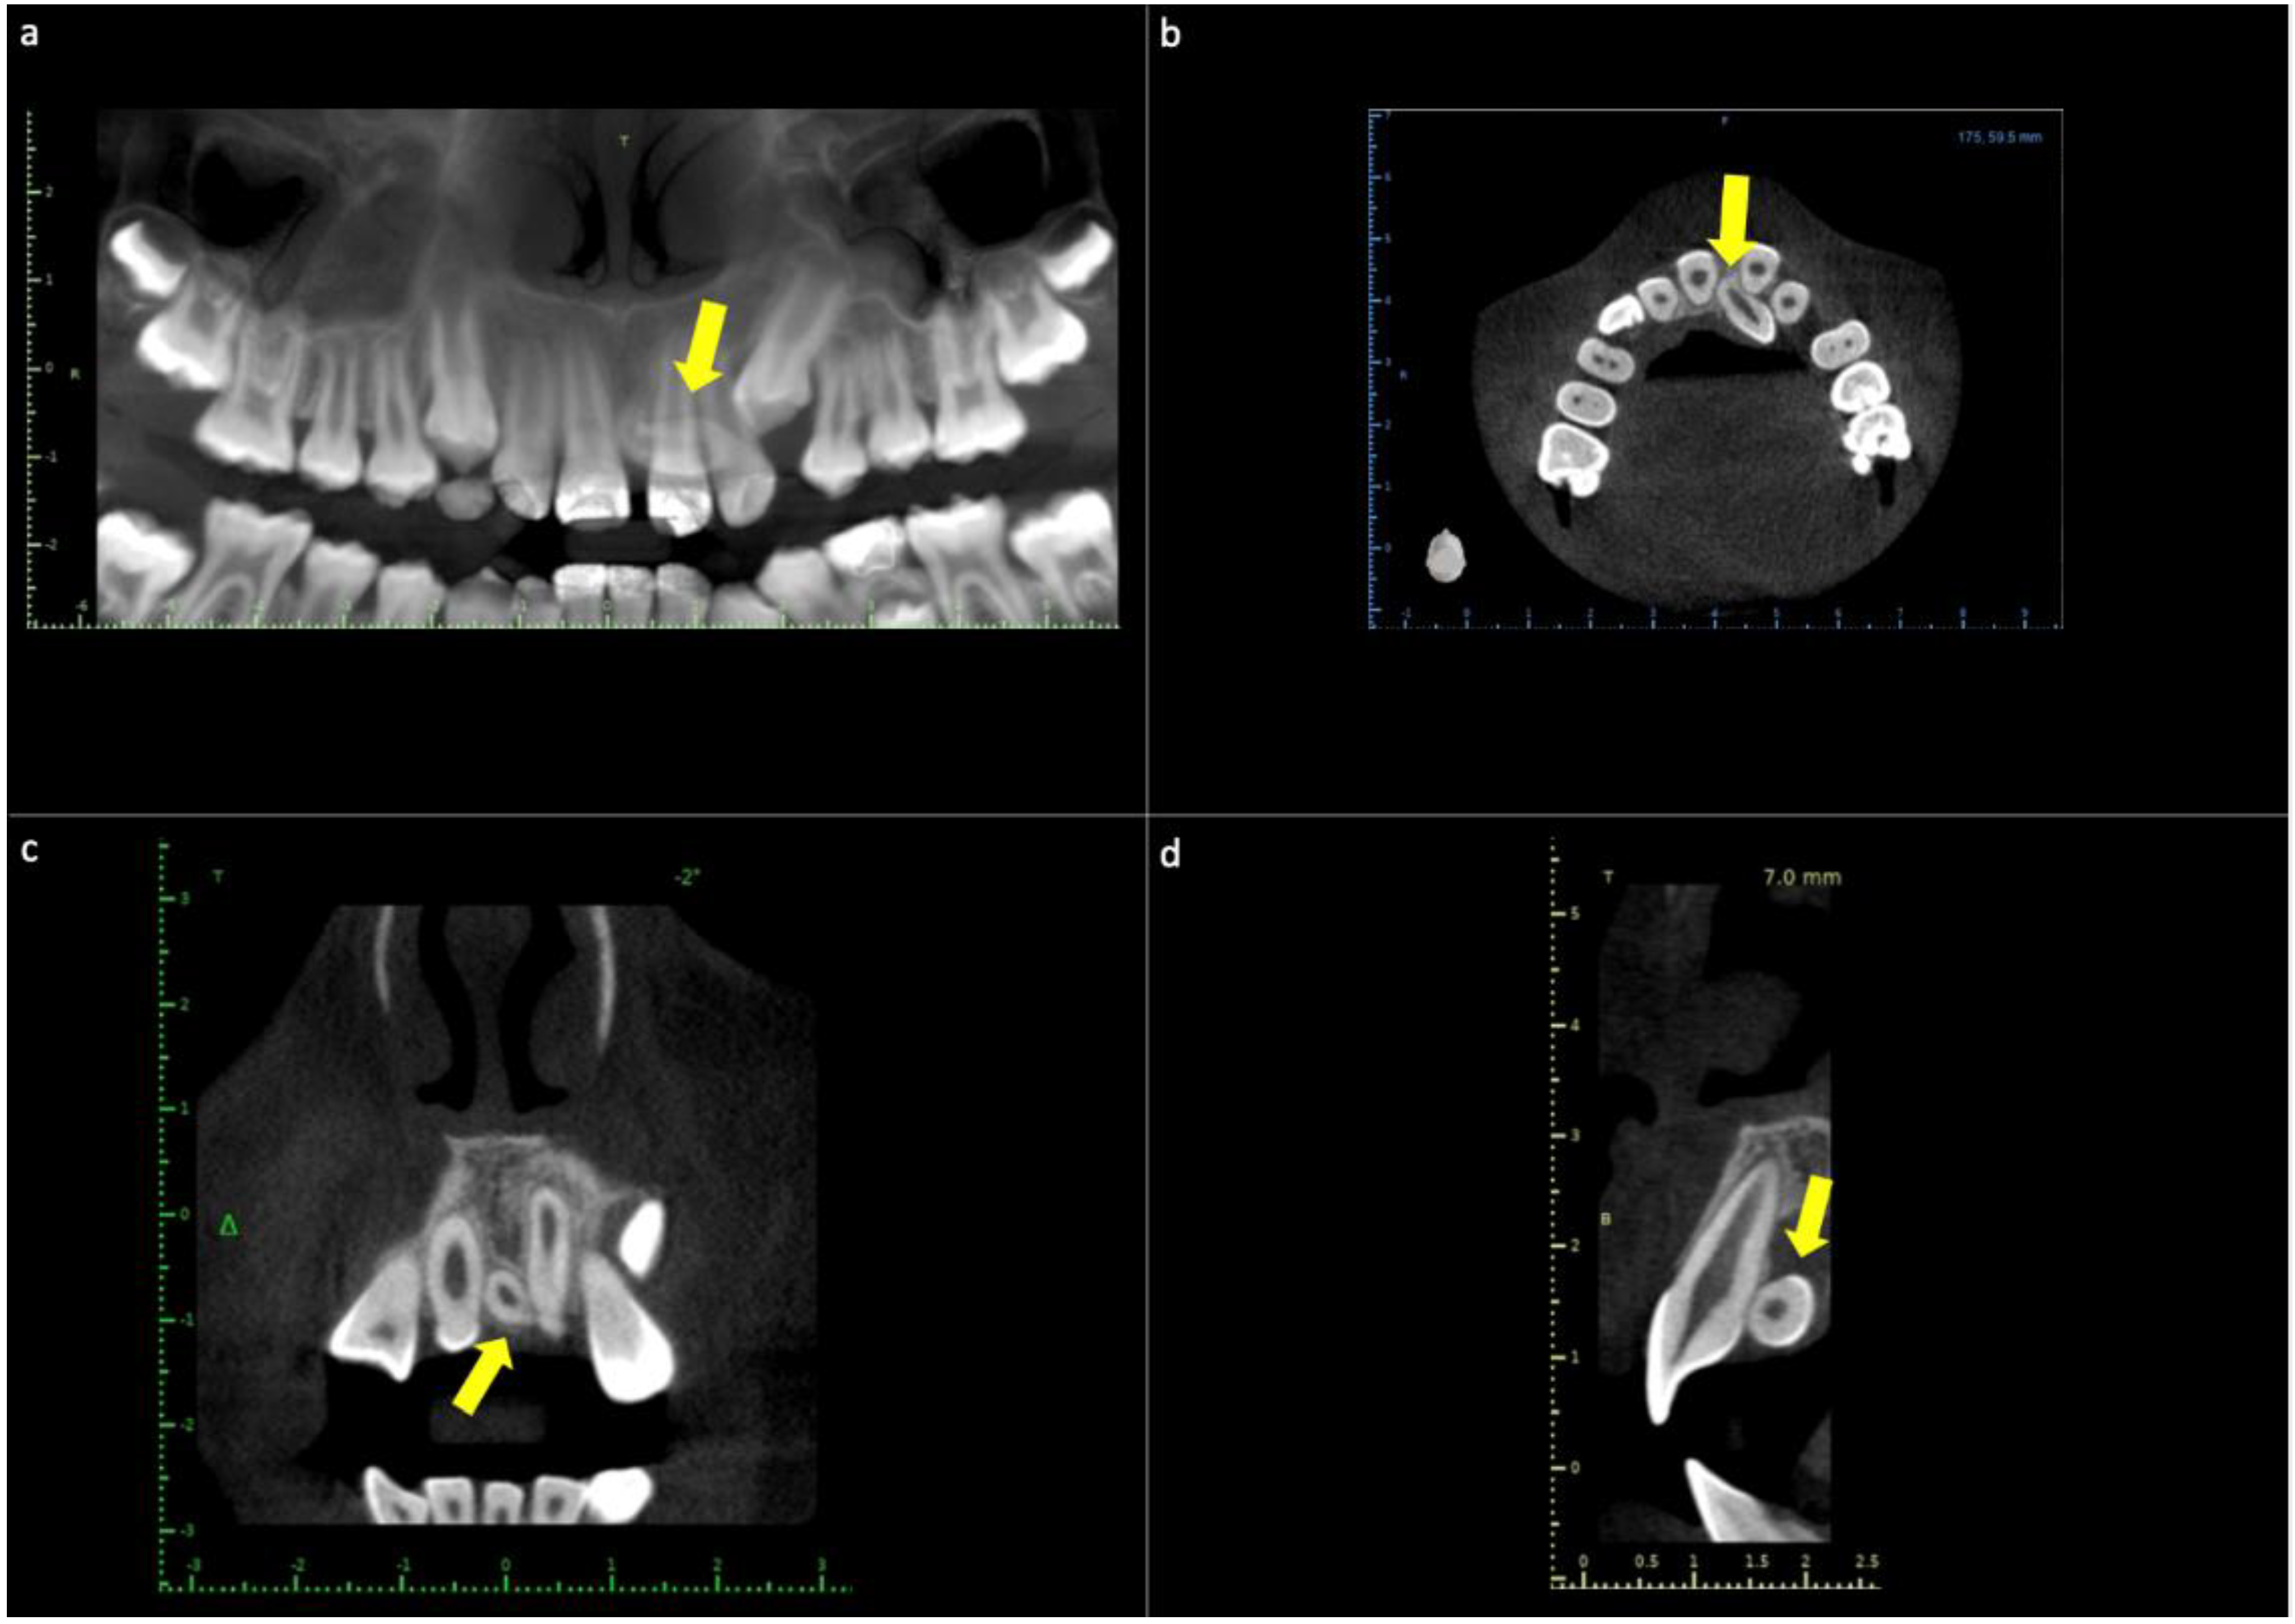

2.3. Case Report 3

| Case Report 3 | Female | Not reported | 12 years old | Radiographic finding | Not reported |